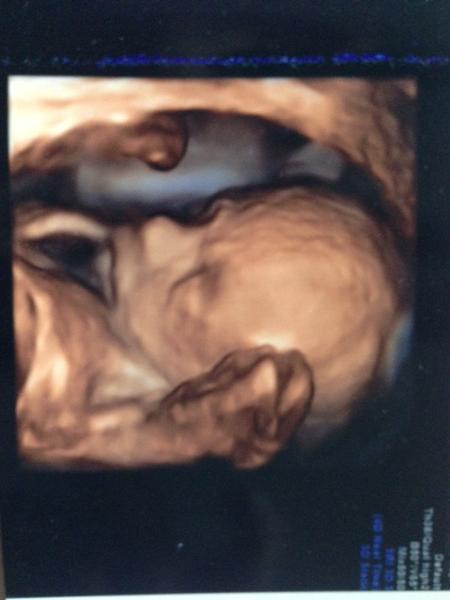

Ahojte 🙂 pridavam sa ako dalsia marcovka ;) budeme mat dievcatko, velmi sa na nu tesime 🙂 mam jeden problemik, snad mi poradite. Uz asi dva tyzdne mavam trpnutie noh ked si lahnem vecer spat. Beriem magne B6 dve tabletky a aj si vykladam hore nohy, no kym to zaberie to su hodiny, neviem sa kvoli tomuto trpnutiu noh vyspat :/ viete nieco poradit? Prikladam fotku fotku malickej z 20tt, teraz sme 23t 🙂

@gabuchah to je nadherne 🙂)) podla bradicky a sanky sa podoba na teba

@babydesire hej? Tak to rada počujem, bo ja v nej zatiaľ vidím iba tatovu pusku a nos 🙂 sa teším až nakoniec budeme po fotkách brusiek, son aj bábätká už 🙂